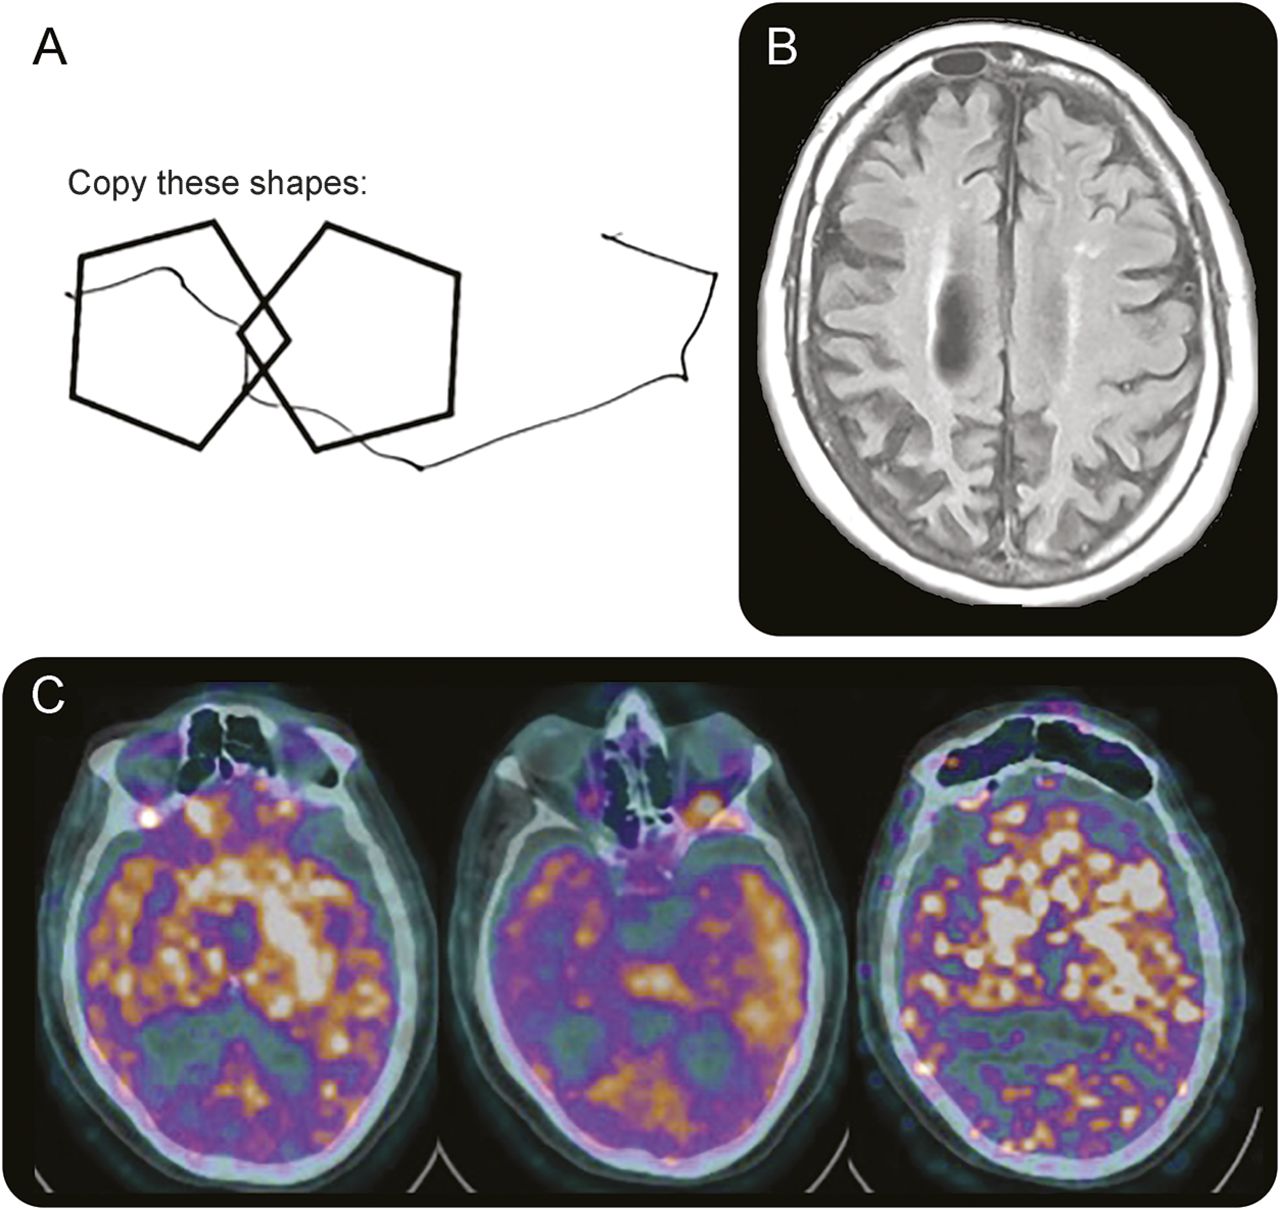

(一)病人被要求复制重叠的五角大楼,展示在视觉空间的建设标志着困难。(B)轴向fluid-attenuated反转恢复MRI显示左大于右顶叶和额叶萎缩,年龄比例。(C)正显示左大于右基底神经节的代谢减退,颞叶,顶叶。

哥伦比亚广播公司(CBS)的特点是不对称帕金森症和皮质赤字。诊断标准区分可能和可能的哥伦比亚广播公司(CBS)。CBS可能需要至少2的不对称表现以下特点:肢体刚度或运动不能,肌张力障碍,或肌阵挛;和下面2:orobuccal或肢体失用症,皮质感觉赤字,或外星肢体的现象。可能由对称的可能的哥伦比亚广播公司CBS建议功能,但只需要一个从每个类别特征。2我们的病人标准可能的哥伦比亚广播公司(CBS)会见了非对称刚度、肌张力障碍,肌阵挛,失用症,皮质感觉赤字,和寄居的肢体的现象。哥伦比亚广播公司(CBS)描述了临床综合征,而CBD是病理诊断。哥伦比亚广播公司(CBS)可能会导致病态CBD,广告,PSP,或者FTLD。我们的病人接受了核磁共振和FDG PET,所示图。

MRI显示全球萎缩不成比例地影响右顶叶包括中央后回(图B)。宠物显示减少示踪剂摄取正确的基底神经节和双边顶叶、左比右(图中,C)。焦不对称顶叶和基底神经节萎缩3和代谢减退4与哥伦比亚广播公司(CBS)一致。